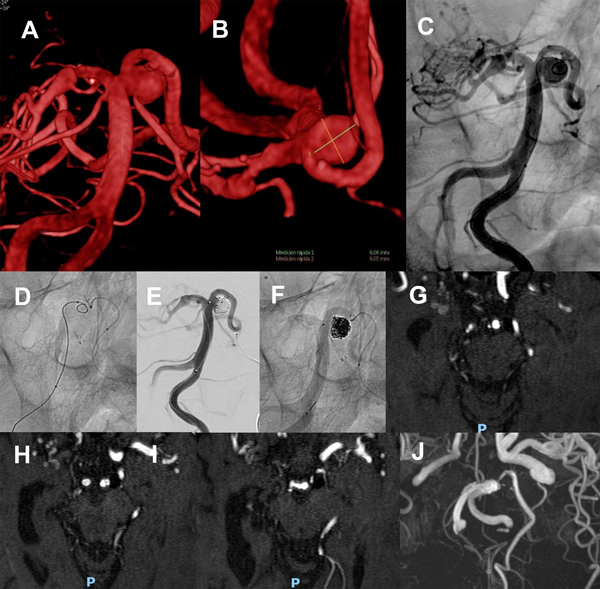

Paciente mujer de 60 años con diagnóstico incidental de aneurismas múltiples, con un aneurisma de mayor tamaño de forma ampular sobre el tronco basilar, en el segmento de cerebelosa superior izquierda, cuyo diámetro es de 6.3 de ancho y 5 mm de altura con cuello de 6.6 mm (AR 0.75, DNR 1), orientado hacia afuera y que eleva el origen de la arteria cerebral posterior izquierda e involucra el origen de la arteria cerebelosa superior izquierda.

Se tomó un doble abordaje con vaina carotídea Shuttle 7F que se posiciona en segmento ascendente de la arteria subclavia izquierda y catéter Guider 6F a segmento suprabulbar de carótida interna derecha. Por este último se navega un microcatéter Excelsior SL10 sobre guía Transend 0.014”, avanzando por la arteria comunicante posterior que es de buen tamaño hacia el segmentoP1 derecho en forma retrógrada y luego se utiliza una guía Hybrid 0.007” para avanzar selectivamente en la arteria cerebelosa superior izquierda.

Dejando este microcatéter posicionado, se asciende con otro microcatéter  SL10 por arteria vertebral izquierda y tronco basilar hasta la cavidad aneurismática, y se asegura la posición insinuando un asa de coil.

En paralelo por el mismo acceso se progresa un tercer microcatéter, en este caso Headway21, avanzado hasta segmento P2 de la arteria cerebral posterior izquierda.

A través del SL10 ubicado en arteria cerebelosa superior izquierda se implanta un stent de malla semi abierta Neuroform Atlas 3 x 15mm, cruzando el tronco basilar hacia el segmento P1 derecho, logrando correcta expansión y con controles satisfactorios en ambas arterias.

Como segundo paso, a través del microcatéter Headway21 se implanta un stent autoexpandible de malla cerrada Lvis de 3.5 x 17mm, descendiendo desde cerebral posterior izquierda por el tronco basilar con buena expansión sobre el mismo y cubriendo toda la extensión del cuello del aneurisma.

Por último, a través del SL10 posicionado en la cavidad aneurismática se inicia la embolización implantando sucesivos microcoils de platino hasta lograr un ovillo compacto que ocupa toda la malformación.

La series angiográfícas de control muestran adecuada oclusión del aneurisma y buena perfusión en todos los territorios, prestando especial atención a las ramas involucradas en el implante  de stents. La paciente se mantiene asintomática, actualmente antiagregada sólo con aspirina, y la DSA a 14 meses confirma oclusión completa (RR 1) (figura 6).

Figura 6. Paciente 15, caso 16. A y B, DSA pre embolización, aneurisma de SCA izquierda tipo PCA- SCA; C, abordaje de SCA izquierda desde PComA- P1 derecha; D, inicio de coiling tras implantar Neuroform Atlas 3 x 21 y Lvis 3.5 x 17; E- F, DSA post embolización, R-R 1; G, control a los 13 meses.

Paciente mujer de 57 años, antecedente alejado de hemorragia intracerebral frontal derecha por ruptura de malformación arteriovenosa frontoparietal, embolizada en otro servicio y posteriormente irradiada, con oclusión parcial. Enfermedad tipo Moya Moya en territorio carotídeo derecho. Grado funcional 2 en escala de Rankin modificada. Aneurisma de cerebelosa superior izquierda con saco de 6 x 5 mm, cuello de 4.4 mm (AR 1.36, DNR 1.3) que incluye los orígenes de PCA y SCA. En consenso con la paciente y familiar se decide su tratamiento.

Con la paciente bajo antiagregación se abordan ambas arterias femorales bajo anestesia general. Tras administrar 10000 UI de heparina endovenosa, se posicionan un catéter Guider 5F en vertebral izquierda y un Guider 6F en carótida izquierda.

Desde este último se navega un microcatéter Excelsior SL 10 con extremo preformado al vapor sobre microguía Transend 0.014”, ascendiendo al sifón carotídeo hasta la comunicante posterior, con road mapping de este territorio en proyección lateral.

A continuación se utiliza road mapping de territorio vértebro- basilar en proyección anteroposterior para guiar el microcatéter sobre una microguía Hybrid 0.007” desde el segmento P1 izquierdo hacia la arteria cerebelosa superior izquierda.

Desde vertebral izquierda se accede con otro microcatéter Excelsior SL 10 con extremo preformado al vapor, hasta ubicar su extremo en la cavidad aneurismática.

Desde el primer microcatéter se implanta un stent de malla semiabierta Neuroform Atlas 3.0 x 21 mm entre la cerebelosa superior izquierda hasta el segmento P1 izquierdo, describiendo una “C” que cubre el cuello del aneurisma y protege el origen de la arteria cerebelosa, y a continuación se implantan microcoils desde el microcatéter “jailed” hasta lograr una oclusión completa, sin observarse alteraciones en la circulación cerebral.

La paciente se mantiene estable, bajo doble antiagregación, y la MRA a 3 meses confirma oclusión persistente (figura 7).

Figura 7. Paciente 17, caso 18. A- C, DSA mostrando aneurisma tipo BA- SCA izquierdo. D, inicio de coiling tras implantar Neuroform Atlas desde PComA- P1 izquierda a SCA izquierda. E- F, post embolización, RR 1. G- J, MRA control a los 3 meses.